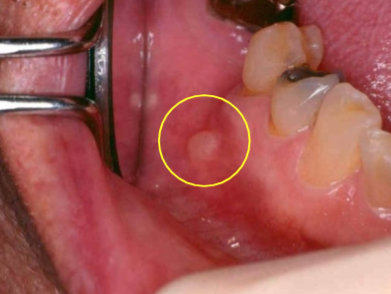

mucocele

due to trauma

especially in children

lower lip most common

bluish, translucent hue

what is a mucocele caused by?

trauma, severance of the duct and spills mucin

mucocele treatment

excision of lesion and minor salivary glands

mucocele image